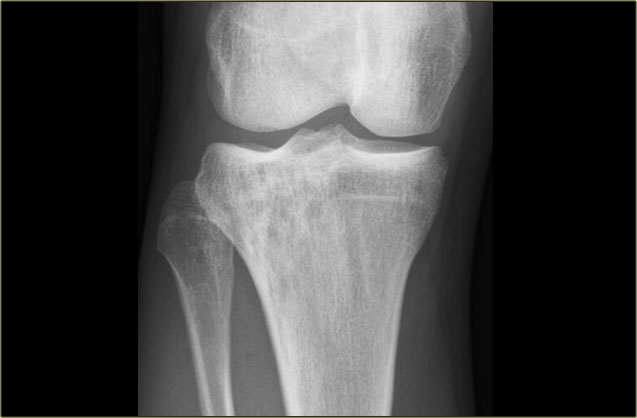

Here a NHL presenting as a non-specific ill-defined mixed osteolytic-sclerotic lesion in the proximal tibia.